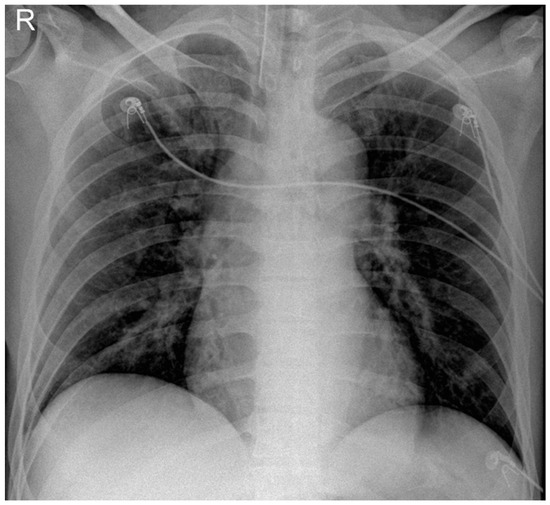

Objectives: To determine the impact of chronic obstructive pulmonary disease (COPD) on incidence, microbiology, and outcomes of ventilator-associated lower respiratory tract infections (VA-LRTI). Methods: Planned ancillary analysis of TAVeM study, including 2960 consecutive adult patients who received invasive mechanical ventilation (MV) > 48 [...] Read more.

Objectives: To determine the impact of chronic obstructive pulmonary disease (COPD) on incidence, microbiology, and outcomes of ventilator-associated lower respiratory tract infections (VA-LRTI). Methods: Planned ancillary analysis of TAVeM study, including 2960 consecutive adult patients who received invasive mechanical ventilation (MV) > 48 h. COPD patients (n = 494) were compared to non-COPD patients (n = 2466). The diagnosis of ventilator-associated tracheobronchitis (VAT) and ventilator-associated pneumonia (VAP) was based on clinical, radiological and quantitative microbiological criteria. Results: No significant difference was found in VAP (12% versus 13%, p = 0.931), or VAT incidence (13% versus 10%, p = 0.093) between COPD and non-COPD patients. Among patients with VA-LRTI, Escherichia coli and Stenotrophomonas maltophilia were significantly more frequent in COPD patients as compared with non-COPD patients. However, COPD had no significant impact on multidrug-resistant bacteria incidence. Appropriate antibiotic treatment was not significantly associated with progression from VAT to VAP among COPD patients who developed VAT, unlike non-COPD patients. Among COPD patients, patients who developed VAT or VAP had significantly longer MV duration (17 days (9–30) or 15 (8–27) versus 7 (4–12), p < 0.001) and intensive care unit (ICU) length of stay (24 (17–39) or 21 (14–40) versus 12 (8–19), p < 0.001) than patients without VA-LRTI. ICU mortality was also higher in COPD patients who developed VAP (44%), but not VAT(38%), as compared to no VA-LRTI (26%, p = 0.006). These worse outcomes associated with VA-LRTI were similar among non-COPD patients. Conclusions: COPD had no significant impact on incidence or outcomes of patients who developed VAP or VAT. Full article

Figure 1